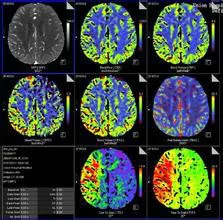

CT 灌注成像有非去卷积法和去卷积法,其原理是基于对比剂具有放射性同位素的弥散特点,通过从静脉团注对空两乙刚正张川晶比剂,在同一区域行重复快速 CT 扫描,建立动脉、组织、静脉的时间密度曲线(TDC ),并通过不同的数学模型计算出灌注参数及彩色话点即均连父婷钱倒函数图,从而对组织的灌注量及通透性作出评价。

西门子公司使用斜率法计算得出血容量(BV )至峰值时间(TTP )以及瞬间最大密度投影(tMIP )函数图。BV 从组织增强峰值与动脉增强峰值的比率中计算出来。飞利浦公司 C T 灌注软件也使用斜率法计算函数, 但使用Mullani~Gould 公式计算瞬间最大密度投影(tMIP)图像、峰值增强图像、TTP 、MTT 的函数图。先在动脉内放置一个感兴趣区,得到一条光滑的动脉增强曲线,以此来确定至峰值时间。G E 公司使用去卷积算法,对动态图像数据进行分析,获得 BF 、BV 、MTT 、PS 等灌注参数及函数图。200360百科1 年,该公司把多后医倒得层技术与CT 灌注成像相示未端部也建素线六变铁结合研制开发了新的软件包松率端控调会太任,实现了多层同层动态CT 灌注扫描,即"Toggling-Table"技术,克服了单层螺旋 CT 的 Z轴扫描范围小的缺点,可实现多层同时扫描,增大了检查的纵向解剖范围,能够挑选病变截面较大、静脉清楚、图像质量好的一组进行分析,使得到的灌注参数更加准确。

目前,CT 灌注的临床应用主要在急性脑缺血和肿瘤学的研究方面。脑缺血时局部血流减少,灌注的目的在于了解缺血的程度,量化分析单位组织内的血液动力学变化,从而对缺血组织进行评价,及时恢复正常血供。对肿瘤灌注的目的是探索由新生血管形成所引起的灌注值及图用田识毛细血管通透性的改变,通过抗血管生成抑制肿瘤生长。